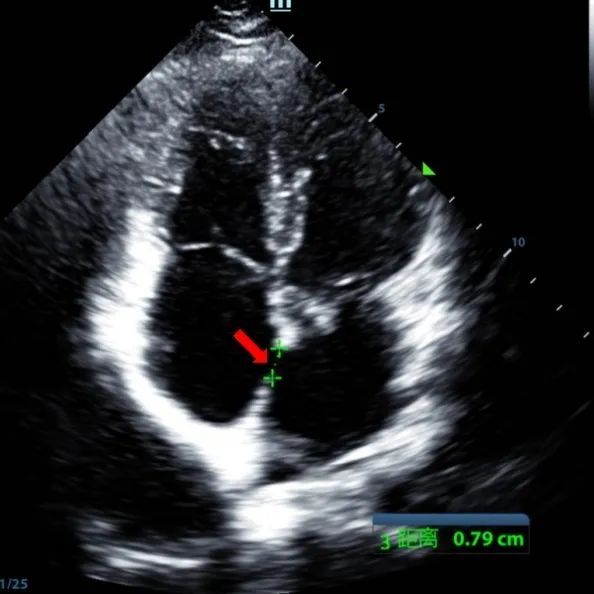

Um homem de 9 anos com ASD secundum (7,5-7,9mm) foi tratado usando um oclusor MemoSorb BDASD-I 12mm e sistema de entrega 12F. Não foram observadas complicações ou comorbidades pré-procedimento.

Serial echocardiographic follow-ups showed stable device position and favorable cardiac remodeling. Gradual degradation confirmed the occluder's long-term safety and efficacy.